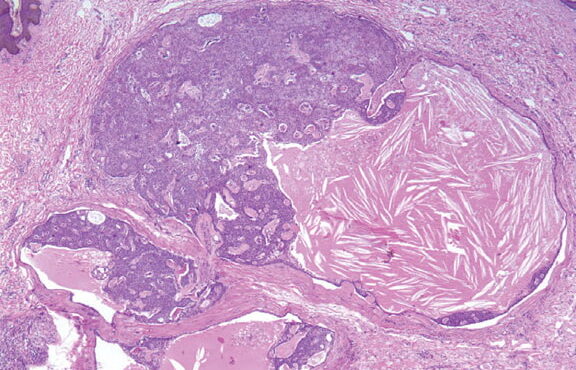

Read MoreSolid cystic hidradenoma = الغدوم العرقي الكيسي الصلب